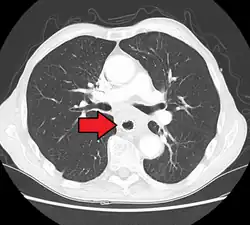

Although an occlusive tumor may be suspected on a barium swallow or barium meal, the diagnosis is best made with an examination using an endoscope. This involves the passing of a flexible tube with a light and camera down the esophagus and examining the wall, and is called an esophagogastroduodenoscopy. Biopsies taken of suspicious lesions are then examined histologically for signs of malignancy.

Additional testing is needed to assess how much the cancer has spread (see § Staging, below). Computed tomography (CT) of the chest, abdomen and pelvis can evaluate whether the cancer has spread to adjacent tissues or distant organs (especially liver and lymph nodes). The sensitivity of a CT scan is limited by its ability to detect masses (e.g. enlarged lymph nodes or involved organs) generally larger than 1 cm.[44][45] Positron emission tomography is also used to estimate the extent of the disease and is regarded as more precise than CT alone.[46] PET/MR as a novel modality has shown promising results in preoperative staging with fair feasibility and good correlation in comparison to PET/CT. It can enhance tissue differentiation with lowering the radiation dose to the patient.[47] Esophageal endoscopic ultrasound can provide staging information regarding the level of tumor invasion, and possible spread to regional lymph nodes.

The location of the tumor is generally measured by the distance from the teeth. The esophagus (25 cm or 10 in long) is commonly divided into three parts for purposes of determining the location. Adenocarcinomas tend to occur nearer the stomach and squamous cell carcinomas nearer the throat, but either may arise anywhere in the esophagus.